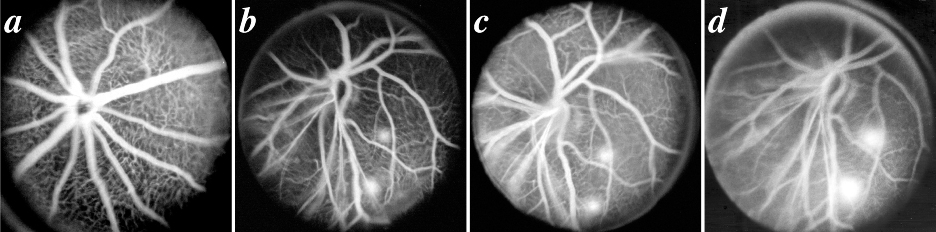

Figure 5. Fluorescein angiograms

A: Normal C57BL/6J mouse eight weeks of age, taken in early venous phase. All retinal arterioles and venules are filled with dye and details of the retinal capillary bed are easily visualized. B-D: Eight week old Onc1 mouse, demonstrating an abnormal blood vessel pattern and two areas of inferolateral fluorescein leakage that become more apparent from early to late venous stages. The angiograms in B-D were taken 143, 183, and 209 s after fluorescein administration.